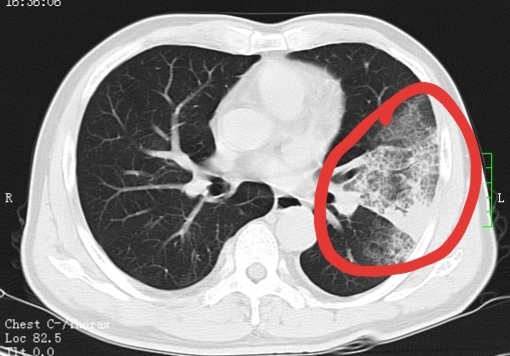

CT结果显示左肺大片状磨玻璃并节段实病灶

此时的黄先生呼吸极度困难,血氧饱和度只有79%,高烧40.5℃,急诊X线显示其左肺大片磨玻璃影并节段性实变、右下肺炎症灶,病情危重,被收入呼吸与危重症医学科-RICU。RICU一边紧急对症治疗, 一边组织全院会诊讨论病情,当务之急是明确诊断,对症治疗,因黄先生平时身体健康,却突然病情危重,考虑罕见病毒、特殊细菌,遂为其进行床旁支气管镜灌洗术检查留取标本,送基因检测明确诊断。